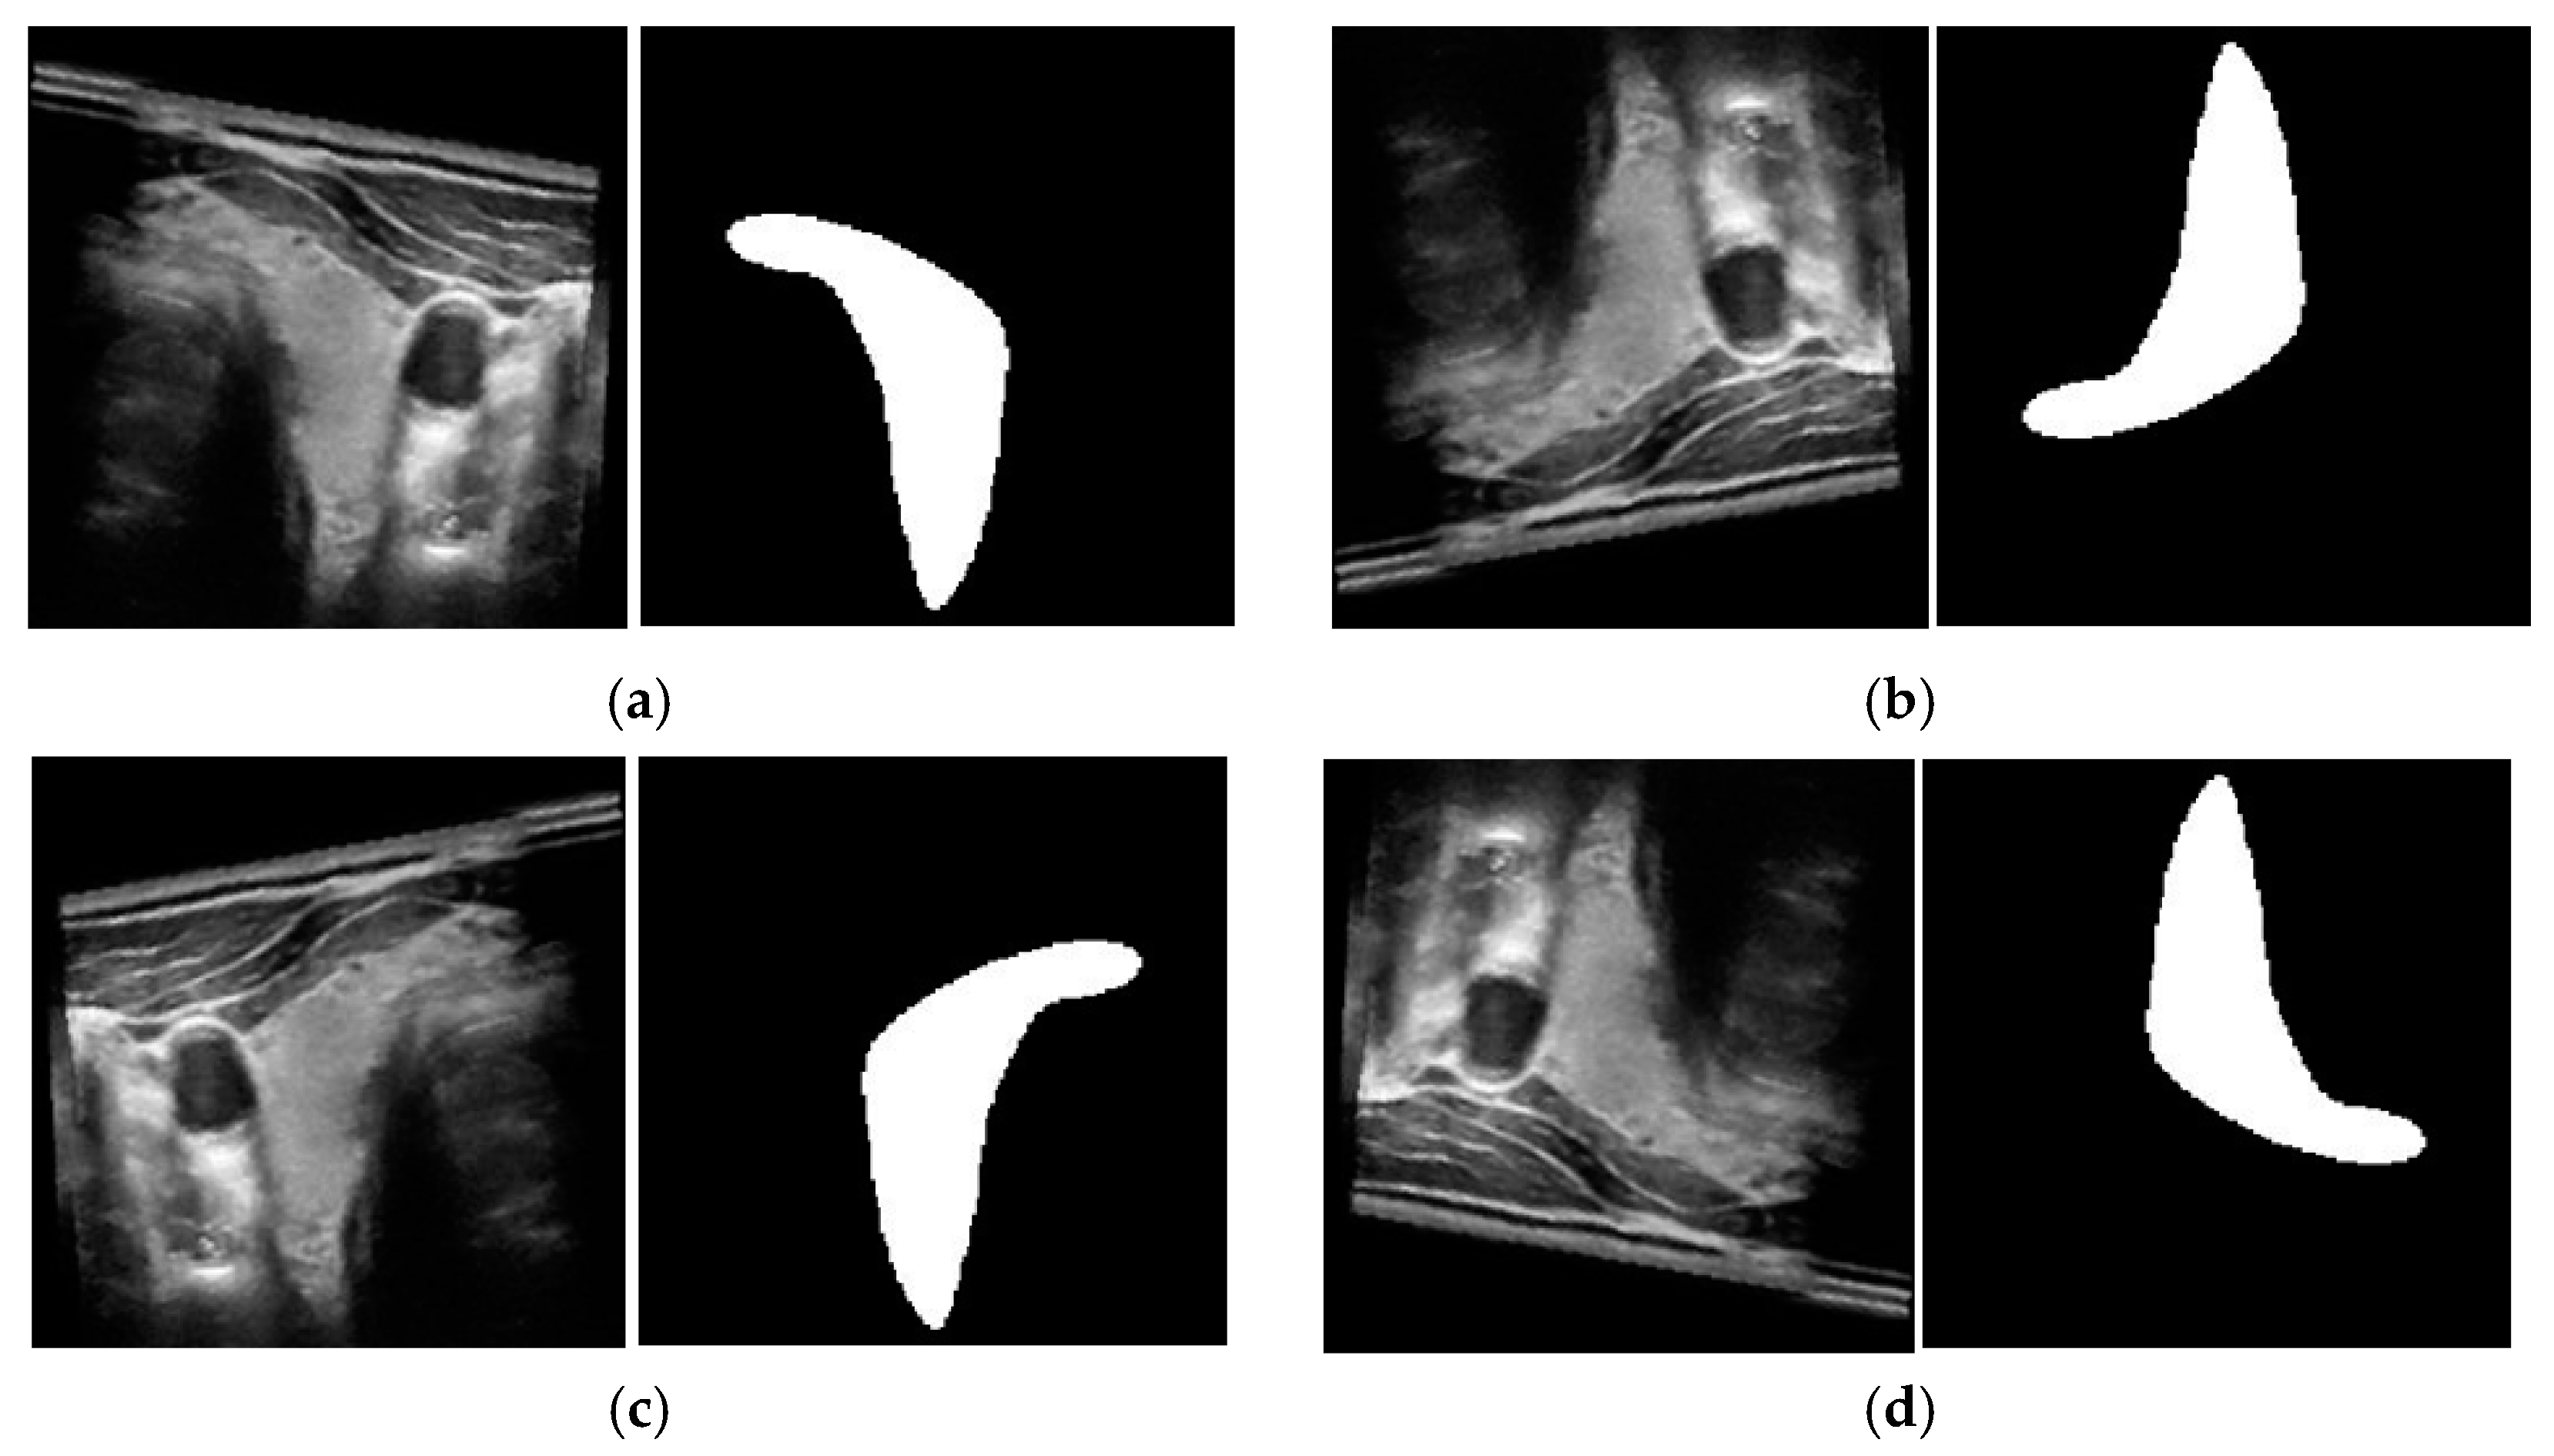

Figure 7.

Examples of images with corresponding ground-truth thyroid region in 3DThyroid dataset.

4.2.1. Analyses of Model Overfitting

We used two public datasets to evaluate the performance of our proposed method. Between the two, the TDID is a smaller dataset with a total of 298 images, and the 3DThyroid is a larger dataset with a total of 15,254 images, as shown in Table 2 and Table 3. The weakness of the 3DThyroid dataset is that it contains 3D volumes instead of individual images. Therefore, the images in a 3D volume of the 3DThyroid dataset exhibit high similarity, and the size of nodule is varied according to the scanning position of the thyroid organ as shown in the Figure 7. The lack of data for training is a common problem with the deep learning method, especially the medical image processing systems. To solve this problem, we adopt the data augmentation, and detailed explanations of this are included in the next subsection. Although we tried to find other public datasets for evaluating our method, we only found the TDID and 3DThyroid datasets which are available for researchers. As shown in Figure 8, we can see that the difference between the training and validation loss of the SN was small (approximately 0.021 with the TDID dataset and 0.148 with the 3DThyroid dataset). With the EN, the difference is also small (approximately 0.057 with the TDID dataset and 0.159 with the 3DThyroid dataset). In addition, we can see from this figure that our proposed method helps to reduce the losses of both training and validation sets. Therefore, we think that our proposed network not only helps to increase the segmentation performance, but also reduces the overfitting problem.

Figure 8 shows that our proposed method had seemingly better overfitting resistance on the TDID than the 3DThyroid dataset. In our study, we designed the SN and EN on the basis of the UNet network architecture, which is a well-known network for medical image segmentation. Therefore, we think that this phenomenon is not related to the network architecture that is more suitable for small datasets. This phenomenon is mainly caused by the characteristics of these datasets. The 3DThyroid dataset contains successive images with nodule sizes ranging from tiny (as shown in the first row of Figure 7) to large (as shown in the second row of Figure 7) nodules, whereas the TDID dataset mainly contains large-sized thyroid nodules as shown in Figure 6. Because it is usually more difficult to segment small-sized nodules than the larger ones, it causes a higher loss of the validation set than that of the training set in the experiments with the 3DThyroid dataset. This is a common problem with segmentation networks.